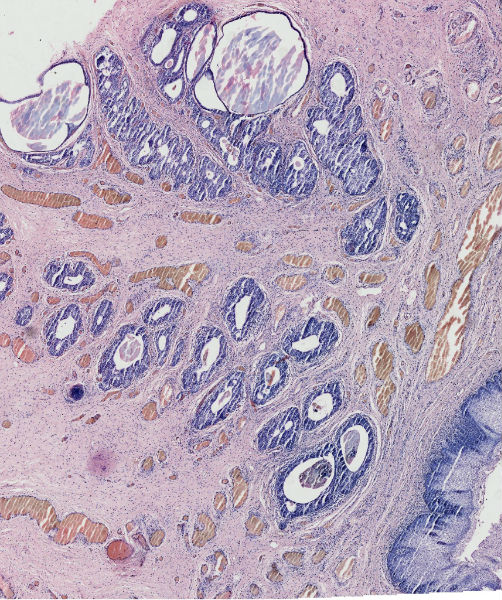

女57岁发现尿道外口息肉二周

• 尿道外口肿物图1

图1

腺囊性尿道炎

上皮下间质中有淋巴细胞浸润,移行上皮巢团中央有柱状上皮围成的腺样腔隙。诊断:腺囊型尿道炎。

支持腺囊型尿道炎